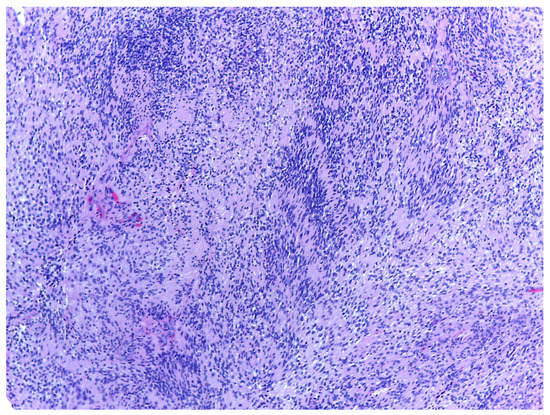

5. Histology